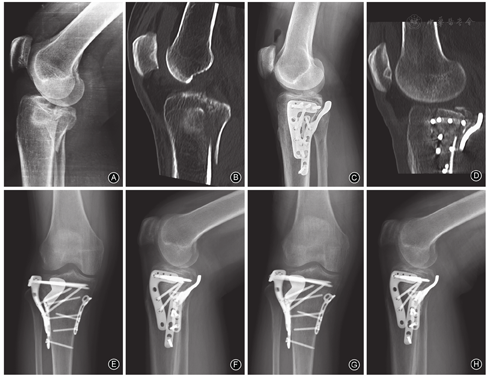

本组10例患者均采用前外侧入路及旋转支撑接骨板固定,其中9例合并外侧平台骨折者加用外侧"L"形解剖锁定接骨板固定(图4,图5),另1例合并胫腓骨及外侧平台骨折者加用外侧4.5 mm"高尔夫"锁定接骨板固定。

本组2例SchatzkerⅤ型骨折患者加用前内侧入路暴露复位内侧平台骨折,其中1例使用3.5 mm"T"形锁定接骨板固定内侧平台骨折,另1例采用前内侧螺钉固定。

本组9例患者关节面塌陷复位后骨缺损区采用同种异体骨植入。

本组患者术后14 d拆线,切口均一期愈合。10例患者均随访满1年,随访时间12~27个月,平均15.25个月。随访过程中无一例发生皮肤坏死、感染、内固定物松动、断裂、骨折复位丢失等并发症。

本组10例患者所有骨折均获得愈合,骨折愈合时间3.0~4.5个月,平均3.2个月。

术后6周复查时,9例患者X线片示骨折块位置良好,无内固定物松动、断裂,遂指导患者开始部分负重行走;术后12周复查时,9例患者X线片示骨折均愈合,指导患者完全负重行走。1例患者术后6周及12周未按时复查及接受相应负重指导,其术后1年复查时X线片显示骨折愈合良好。

末次随访时,患者膝关节活动度105°~161.4°,平均139.9°。HSS评分为64~98分,平均88分;其中优8例,可2例,优良率为80%(8/10)。HSS评分较低的2例患者,其中1例原因考虑与术后6周及12周未复查,未能接受功能恢复锻炼指导有关;另1例患者在接受功能恢复锻炼指导后,因担心再次骨折,未按指导及时进行膝关节活动锻炼。